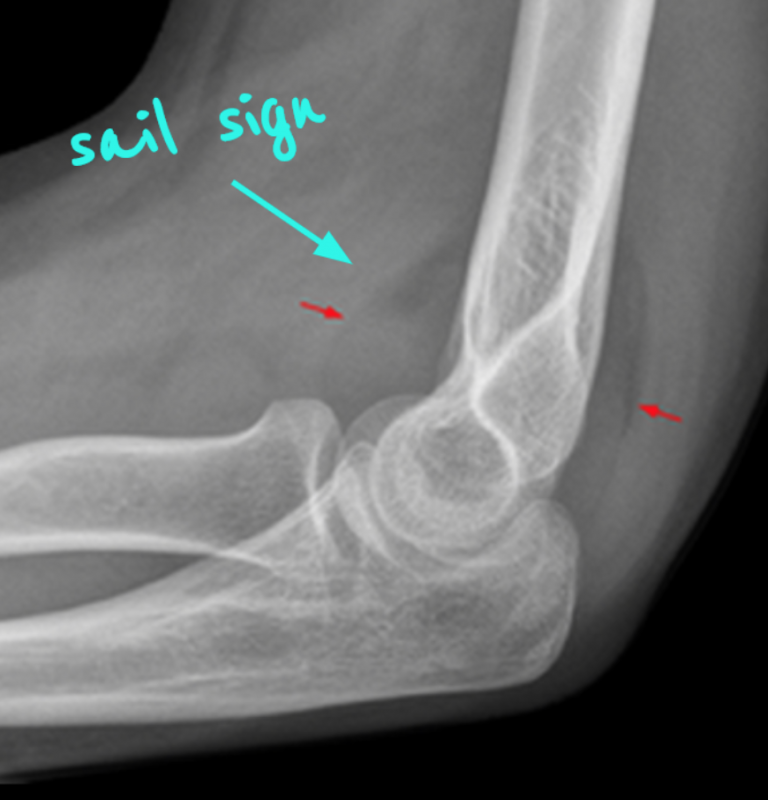

Elbow X Ray Guidelines . the elbow series is a set of radiographs taken to investigate elbow joint pathology, often in the context of trauma. Fractures lines can be difficult to visualize after acute elbow injury, particularly in children. To assist in choosing the appropriate test for specific clinical. an elbow series is the standard series of radiographs that are performed when looking for evidence of fracture, dislocation or elbow joint. In this view, the patient is supine on the table with the arm abducted 90° from the body and the forearm supinated. The upper arm rests on the. Check the anterior humeral line: Anteroposterior (ap) and lateral radiographs remain the workhorses of elbow imaging.